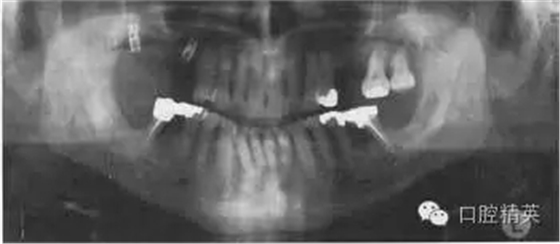

圖38.2 患者牙齒的全口牙位曲面體層X線片

牙齒全口牙位曲面體層X線片如圖38.2所示,你看到了什么?

答:全口牙位曲面體層X線片不是很清晰。患者頭位沒擺正,使圖像產(chǎn)生很大扭曲。下頜骨下緣呈彎曲圖像,且下前牙被縮短了。因為體位不正,脊柱陰影也被增強了。因為影像重疊,中線處的牙齒沒在中點。頭偏向一邊,一側(cè)影像被放大。這在后牙牙冠上很容易看出來,因為右側(cè)比左側(cè)的牙冠大?;颊叩男g(shù)后片如圖38.3,它顯示了正常片子應(yīng)顯示的樣子。

X線片顯示,了右下及左下第二磨牙周圍廣泛的骨質(zhì)破壞。左下第二磨牙有骨喪失并有根分叉處齲壞。下頜兩個第一磨牙有明顯的根分叉病變,但卻不松動。